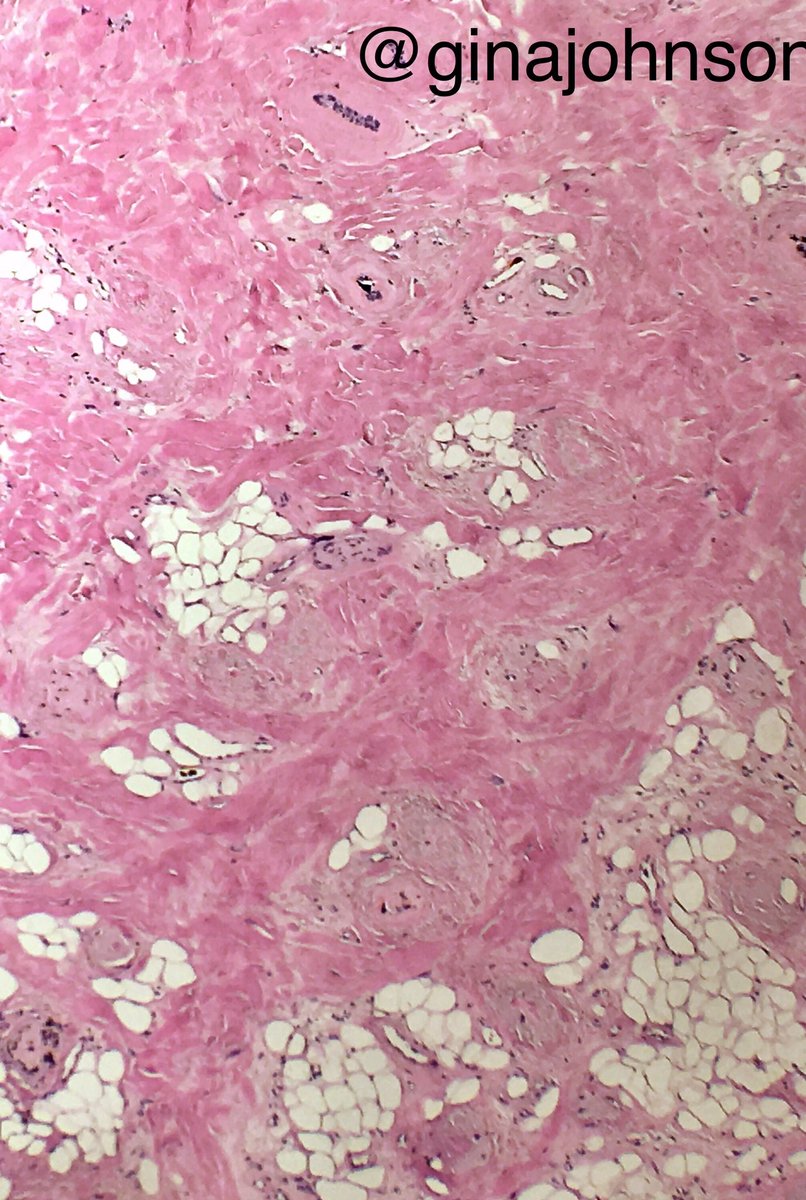

Pop quiz: Alopecia bx. R/O metastatic breast ca. What's going on here, @LenSperling ?

ginajohnsonmd's tweet image. Pop quiz: Alopecia bx. R/O metastatic breast ca. What's going on here, @LenSperling ?